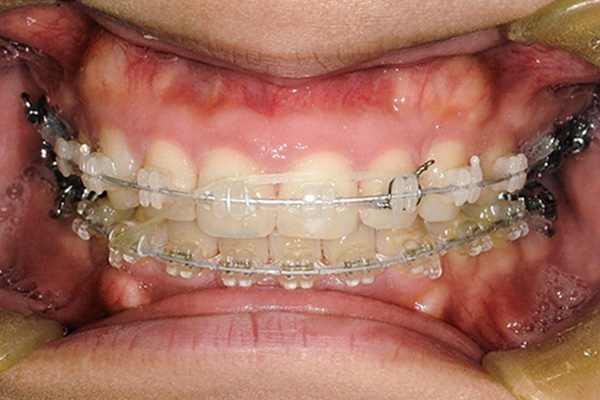

20代 女性

| 症状 | 下顎第一大臼歯の欠損 |

治療経過

42ヶ月後